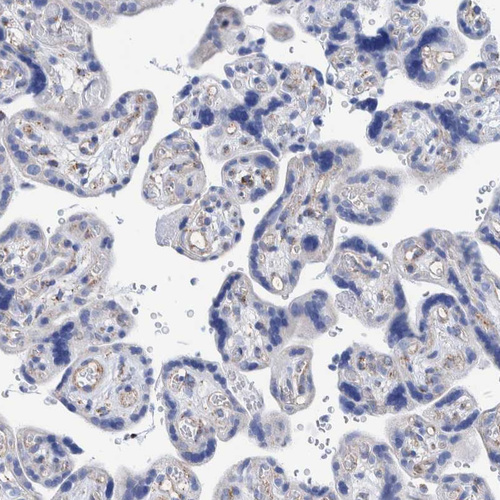

Immunohistochemistry analysis in human liver and placenta tissues using HPA023238 antibody. Corresponding DECR1 RNA-seq data are presented for the same tissues.